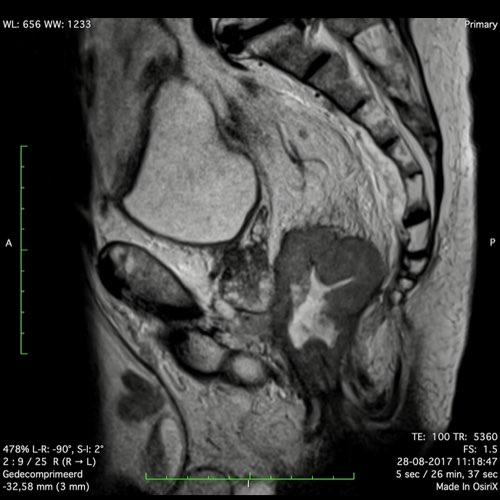

Hình ảnh

Các hình ảnh được cung cấp cho thấy ung thư biểu mô tế bào nhẫn với tình trạng dày lan tỏa thành trực tràng, hình ảnh bia bắn điển hình, và sự xâm lấn mỡ mạc treo trực tràng.